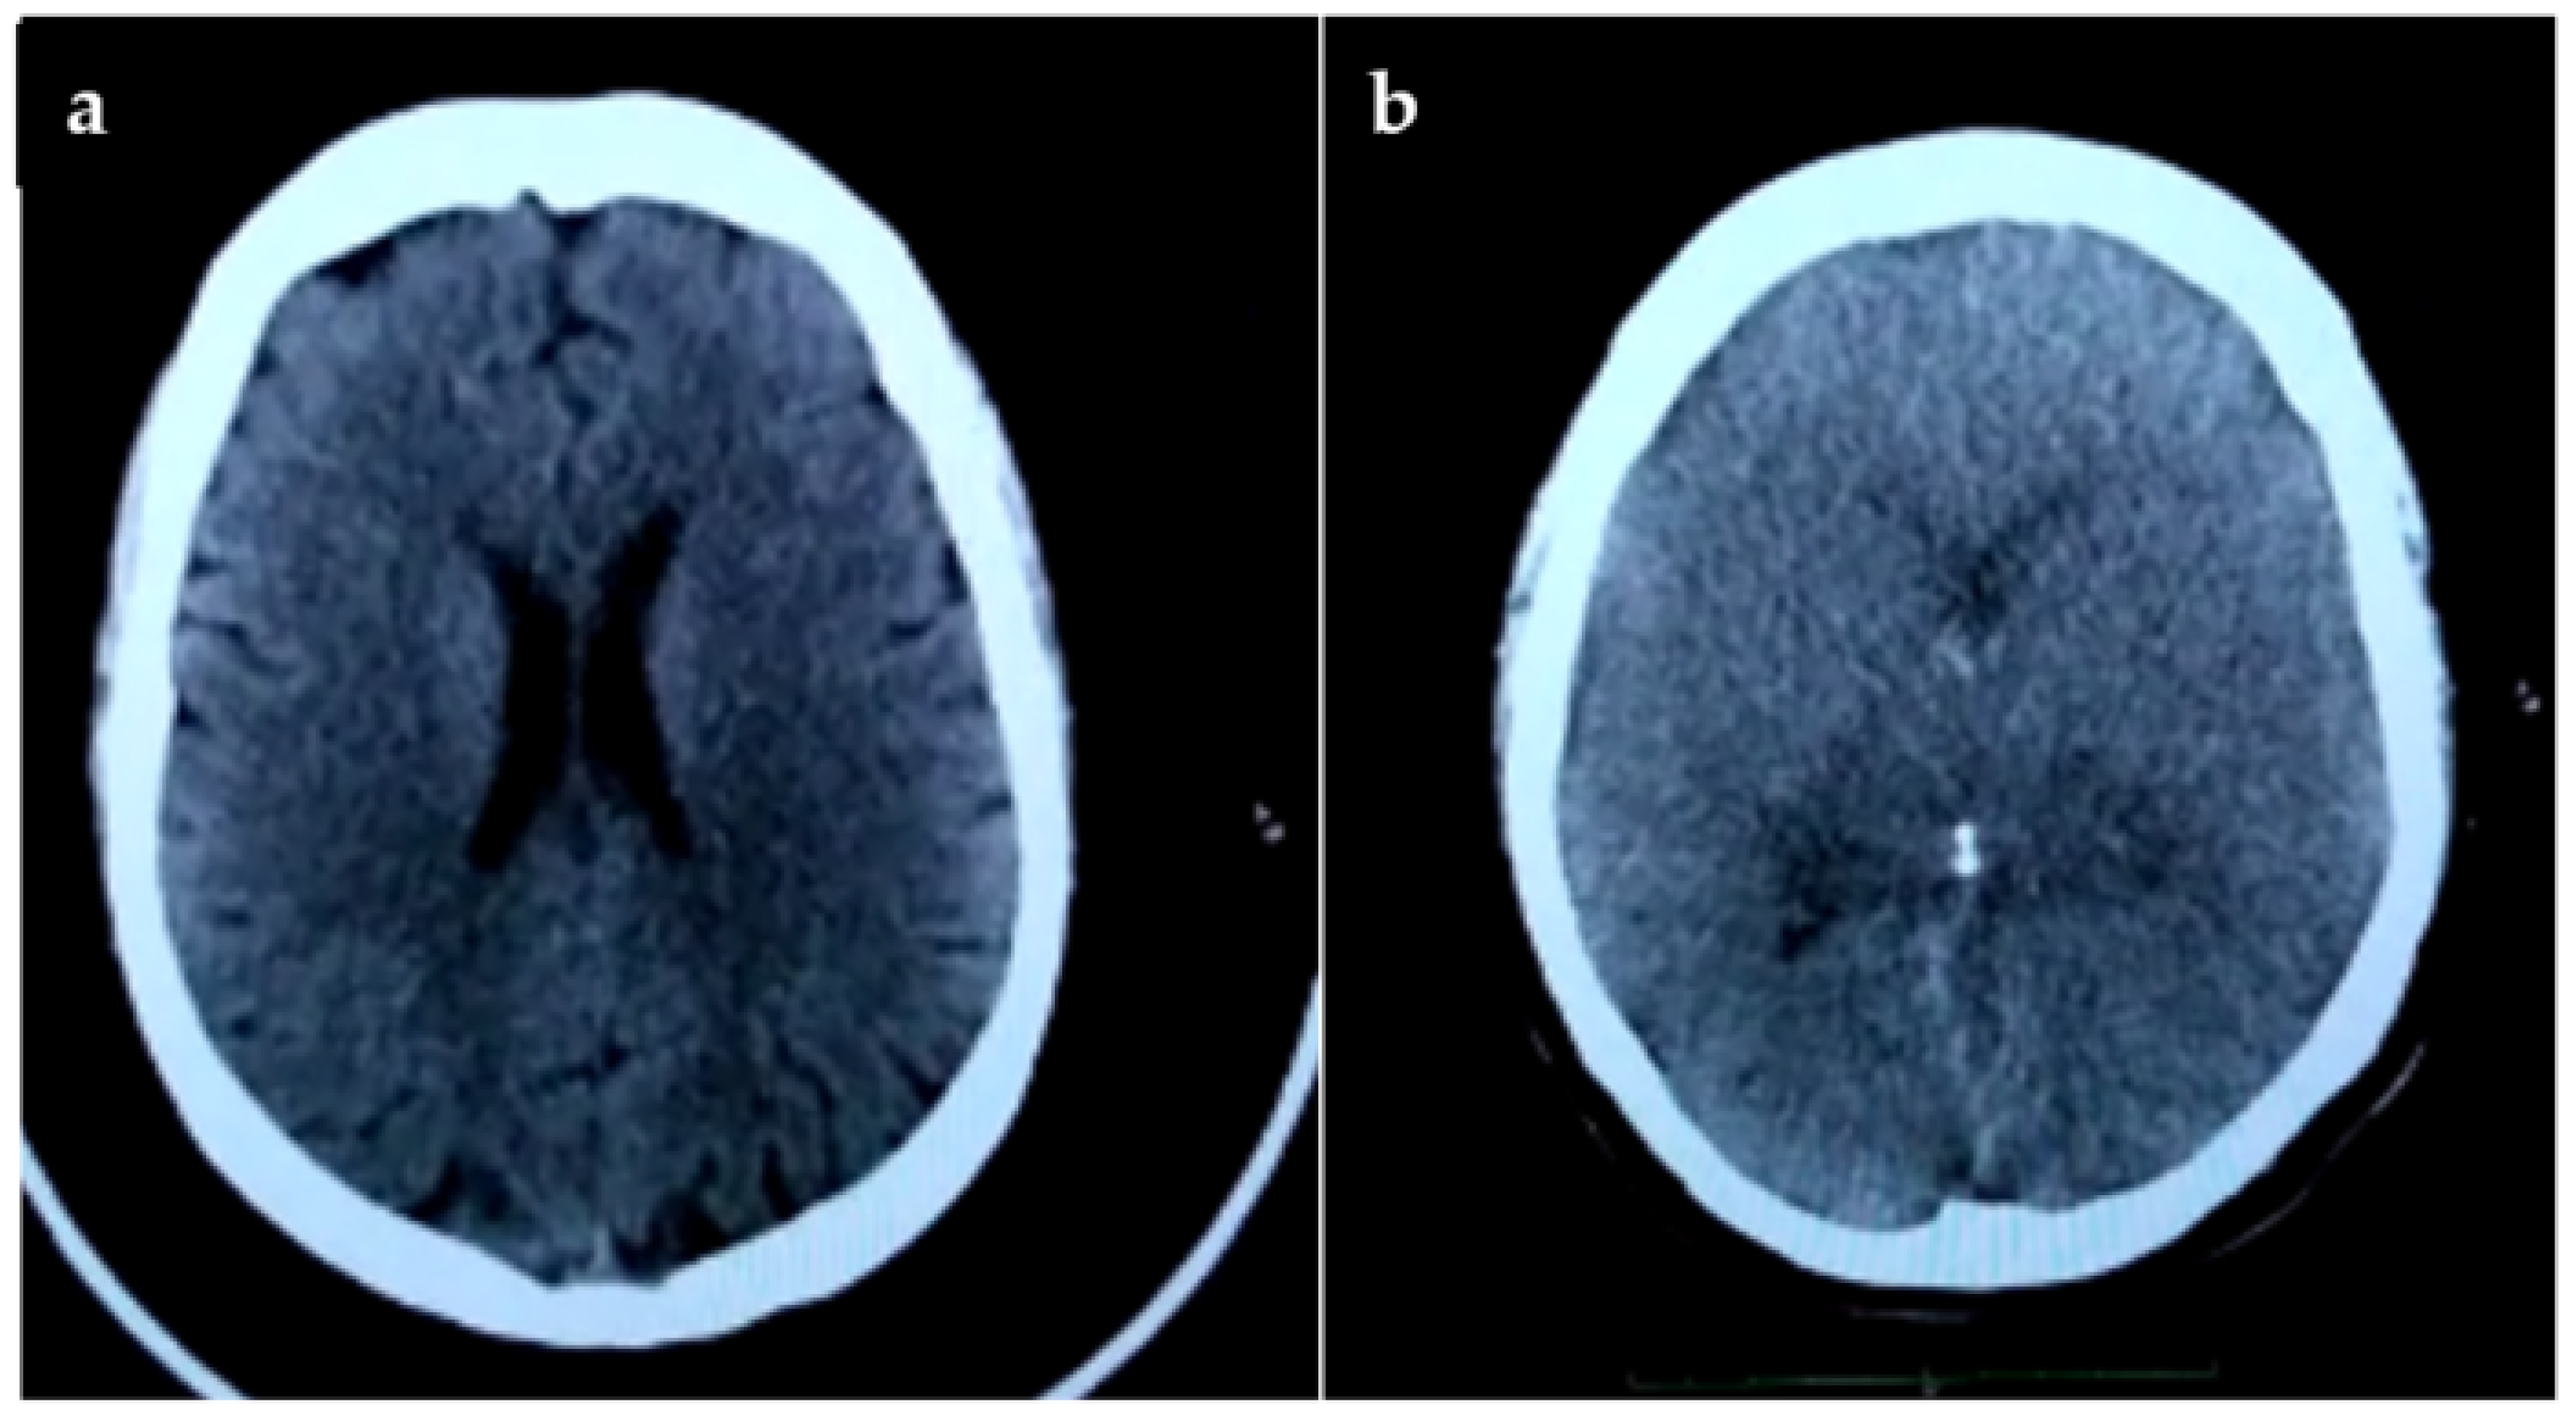

2. Case Report